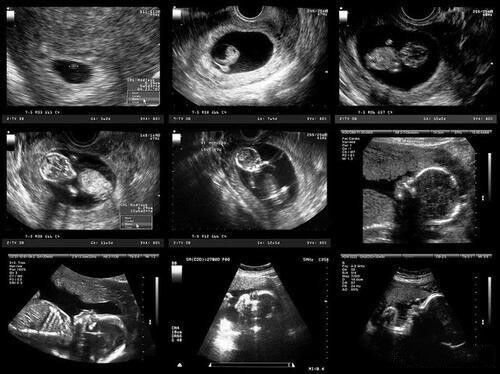

B超单是孕妈妈与胎儿的第一次亲密接触,当知道宝宝的健康状况后,就只有对宝宝性别比较好奇了。但是医生是不会直接和你透露宝宝的性别,正能靠自己去猜测,于是有经验的准妈妈们总结了判断男女的方法。给大家整理出来了,一起往下看看吧。

孕囊形状法

怀孕两个月左右进行B超检查时,孕囊的形状或许藏着小秘密!如果孕囊形状呈现出长型,宛如茄子或长条状,那肚子里很可能是个男宝宝;反之,要是孕囊是椭圆或圆形,女宝宝的可能性就更大啦。

长宽数据法

仔细观察B超数据单,上面记录的孕囊长宽数据也有“门道”。当长宽相差一倍以上时,男孩的概率直线上升;要是长宽数值基本相等,那大概率会迎来一个可爱的女宝宝。